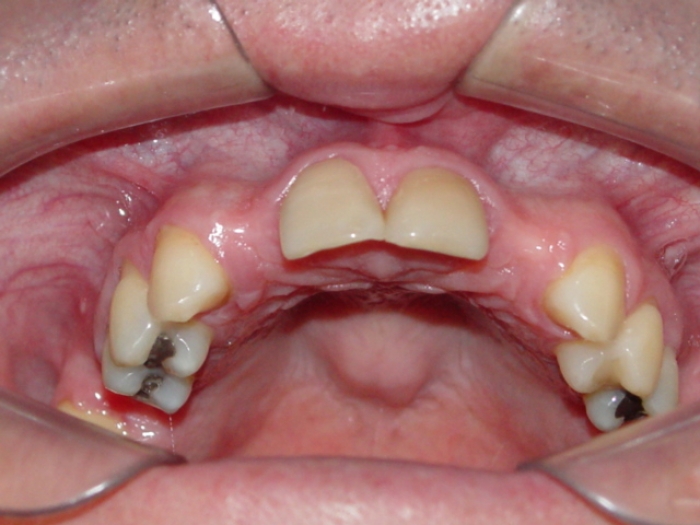

Imagens iniciais